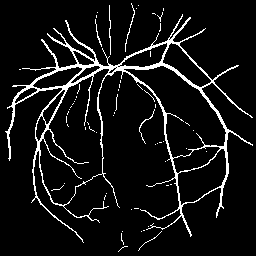

FIVES dataset [14] consists of 800 high-quality multi-disease fundus images and annotated segmentation masks. We partition this dataset into 70% for training (560 images), 10% for validation, and 20% for testing. Similar to ACDC, we use 5% (28 images) and 10% (56 images) of the 560 training images as labeled data to simulate low-data availability, treating the remaining data as unlabeled.

Synthetic Data: For our experiments, high-fidelity synthetic images are generated using StyleGAN2-ADA [16] as described in Section 3.1.2. The model is trained exclusively on the limited percentage of real labeled data available for each dataset (e.g., 5% or 10%). For instance, when using 10% labeled data (136 images for ACDC or 56 for FIVES), StyleGAN2-ADA is trained solely on these specific images. Figure 3 shows random synthetic samples generated for both ACDC and FIVES datasets at 5% and 10% labeled data splits.

Quantitative Results: Table 2 shows that SRA-Seg achieves the best DICE scores among all methods using synthetic unlabeled data in both 5% and 10% splits, even outperforming methods using real unlabeled data.

Qualitative Results: Figure 7 provides qualitative segmentation results on the FIVES dataset. Consistent with our quantitative analysis, these visualizations highlight SRA-Seg’s superior performance in accurately segmenting various anatomical structures compared to other approaches.